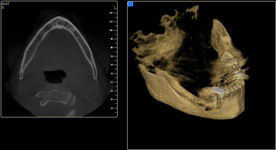

Nejčastější oblastí pro doplnění kosti je čeleni dutina horní čelisti.

Tento výkon se nazývá sinus lift - aplikace kostního granulátu do čelistní dutiny

Při ztrátě molárů a premolárů v horní čelisti a jejich náhradě implantáty se často setkáváme s nedostatečnou vertikální nabídkou kosti pod čelistní dutinou, často doprovázenou i nedostatečnou horizontální nabídkou a sníženou kvalitou kosti

(v oblasti 2. premoláru v 50%, v oblasti moláru až v 80% případů nedostatečná kostní nabídka)

Od roku 1985 je tento problém řešen augmentační operací nazývanou sinus lift.

Jedná se o vyzvednutí membrány, která čelistní dutinu vystýlá, pod vyzvednutou membránou vznikne kapsa, kam se umístí augmentační materiál, do kterého se zavedou implantáty.

Vhojení implantátů se při této operaci prodlužuje na 6-12 měsíců.